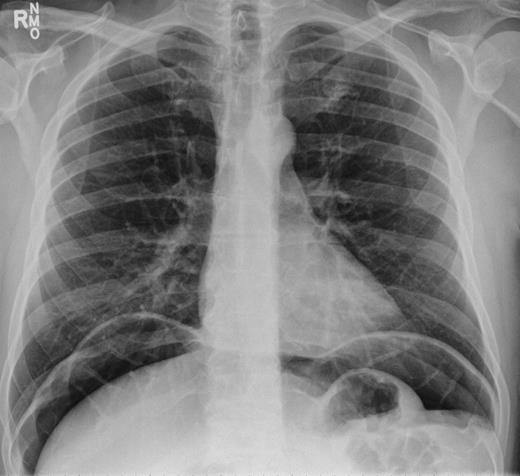

He was taken for urgent laparotomy to evacuate the free gas and aid diagnosis. The bowel was extensively examined and no evidence of perforation was found. The abdominal wall was closed and he returned to the ward. Subsequent X-rays showed that the pneumoperitoneum had resolved. Post-operatively his CRP level was 226 and he went into ileus requiring nasogastric tube placement (Fig. 3). With recurrence of normal bowel activity and with settling of his symptoms, he was discharged.